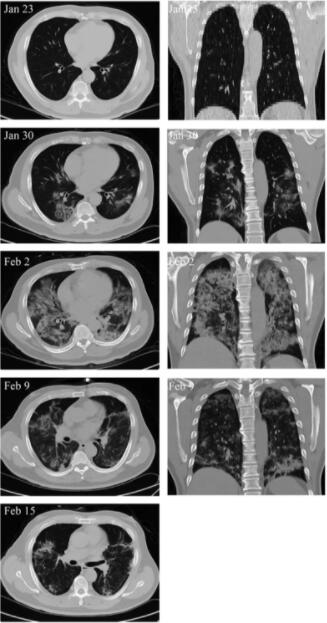

另外,MSC移植能顯著加快治療進程。移植后4天,新冠肺炎危重癥患者呼吸頻率降至正常范圍、發燒和呼吸急促等癥狀消失。移植后9天,胸部CT成像顯示毛玻璃樣混濁和肺炎浸潤已大大減少。

危重患者肺部影像學顯示癥狀改善